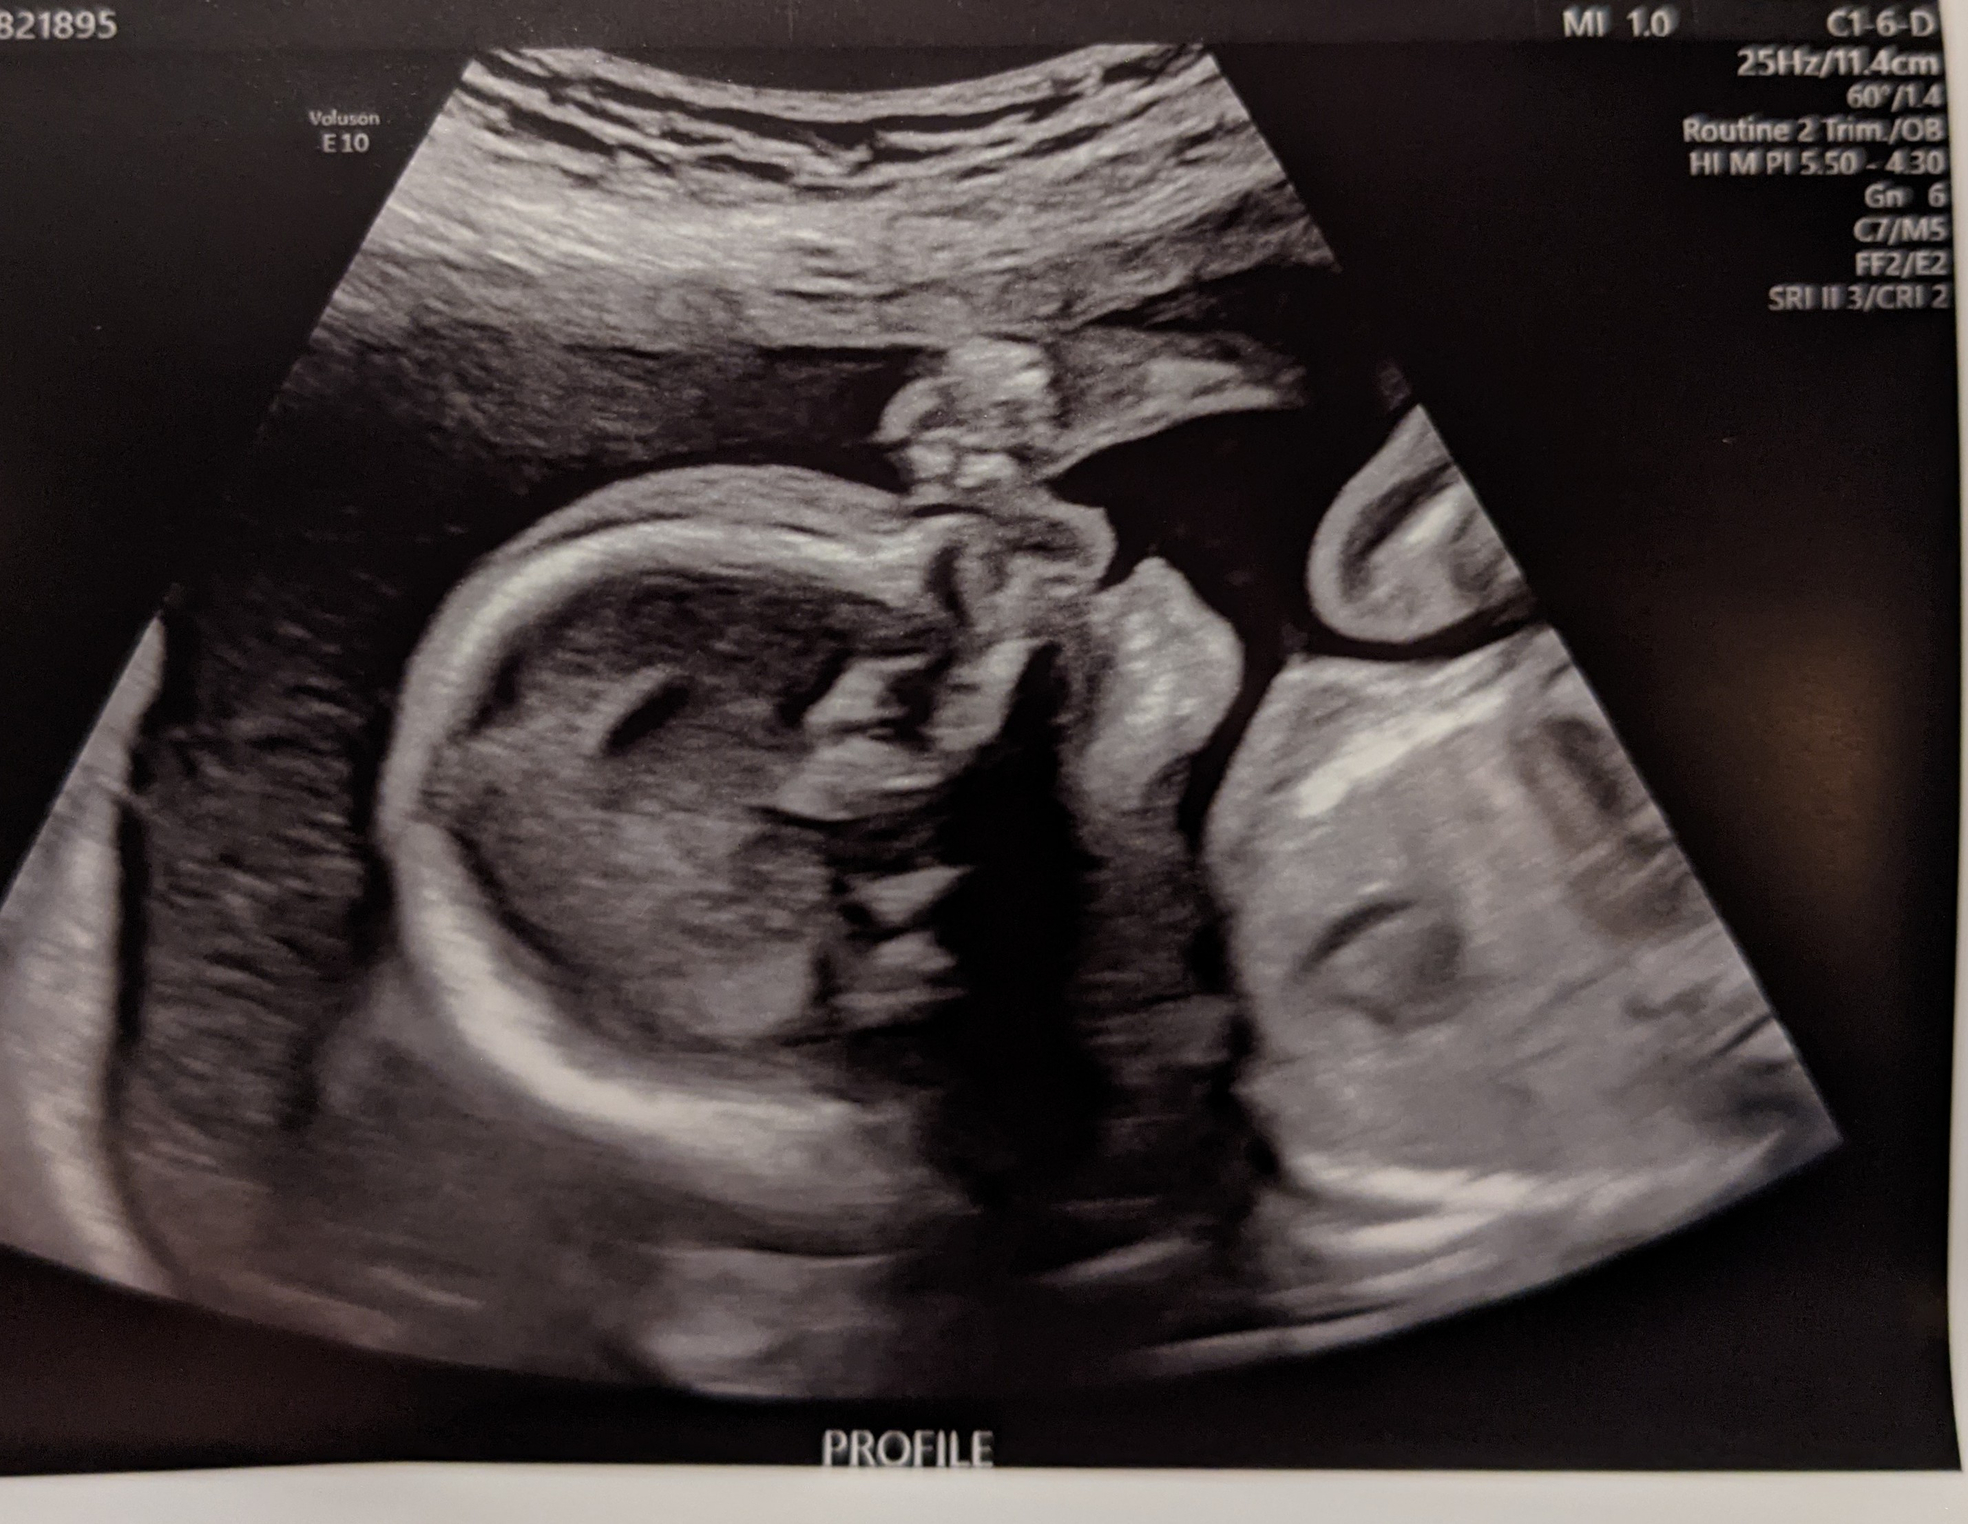

I had my anatomy scan. He is measuring big in the 78th %tile and absolutely perfect. He was moving so much she struggled to get some measurements. She got some incredible 3D pictures of him. Look at that sweet face! 😍

20 week scan today with MFM plus fetal echocardiogram, and no issues to report! Baby boy #2 ... And he's smiling! 99th percentile just like his brother.

AS today and baby looked great and healthy! We stayed Team Green for the 4th time. The tech said she could definitely tell if it was a boy or girl, but I stayed firm and told her we for sure didn’t want to know! This was the very first time I’ve had a 3D ultrasound- Baby has similar features to his/her big sisters! Can’t wait to hold this cutie in 20 weeks 🥰